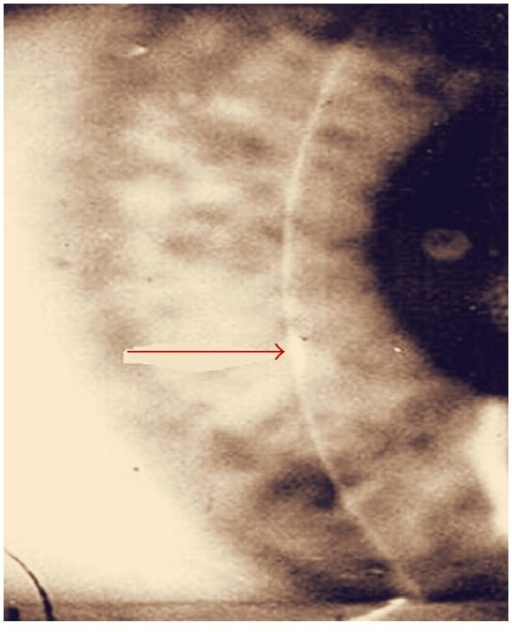

- Ghost vessels: 비활동 혈관 — 이전 IK를 시사하는 가장 특징적 후유증

Ghost vessels = 이전 간질각막염의 흔적. 세극등에서 혈액이 없는 빈 혈관으로 보임. 과거 매독 이력을 시사하는 중요한 소견.